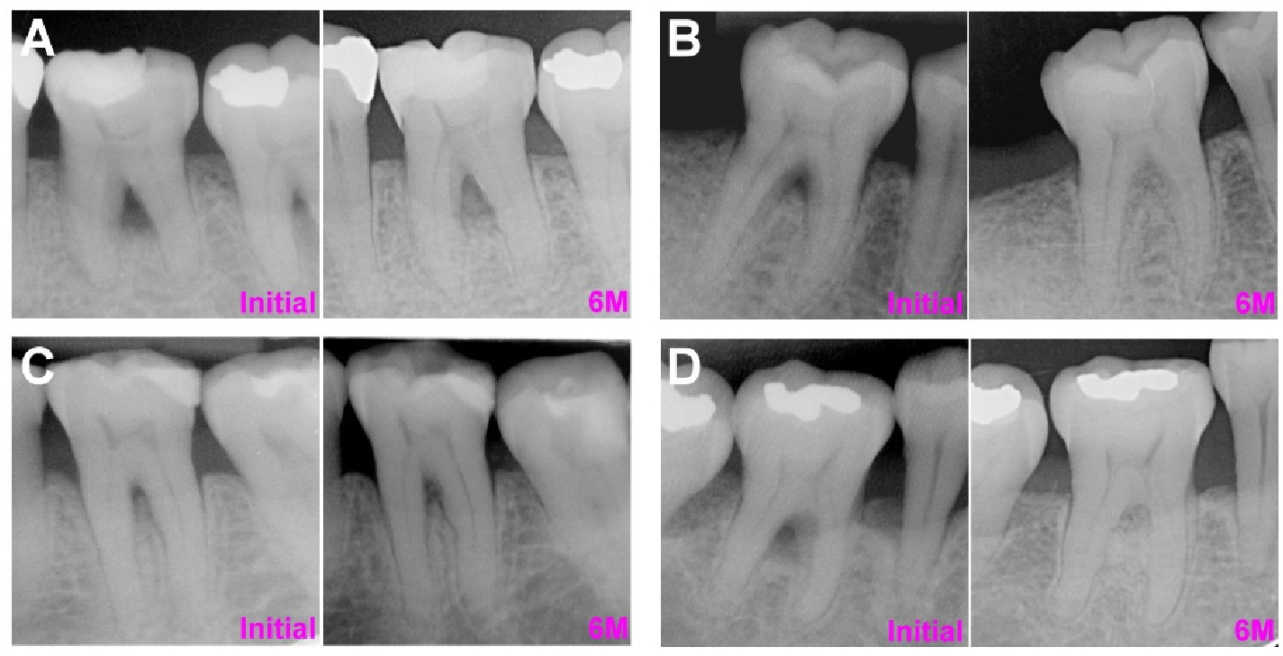

- Radiographic records of furcation defects in the examined teeth before and at least 6 months after the regeneration procedure were available.